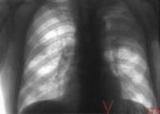

Своевременное обращение дает дополнительные гарантии, что туберкулез вылечат.

– По критериям ВОЗ в 1995 году зарегистрировано эпидемию туберкулеза, – рассказал Виктор Лысак, начальник Главного управления...